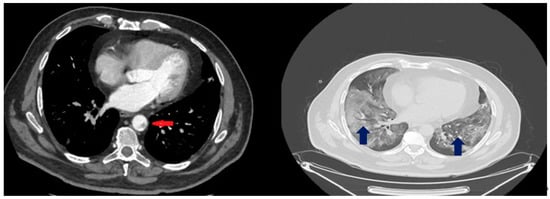

| Day 43 | CTPA: Residual ground-glass opacity lesions, fibroatelectacic lesions at the right lower and middle lobe, traction bronchiectasis at right middle lobe and lingula of left lobe. No presence of thrombi at the thoracic aorta. Abdominal and pelvic CT scan: Splenic and renal infarct (along with renal cortical thinning) are depicted again. Re-tunelling of the splenic vein. |